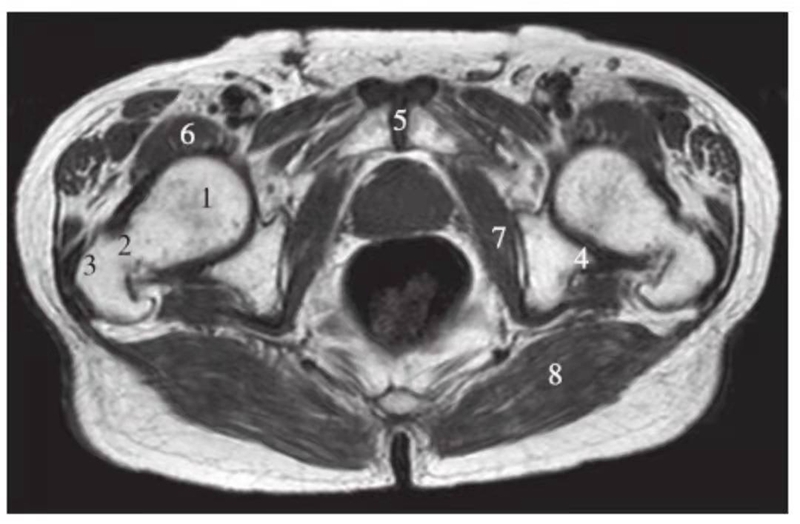

矢状位

正常髋关节经股骨头内缘层面T1WI像

1.髂骨;2.臀大肌;3.圆韧带;4.股骨头;5.坐骨;6.闭孔外肌;7.耻骨肌;8.大收肌